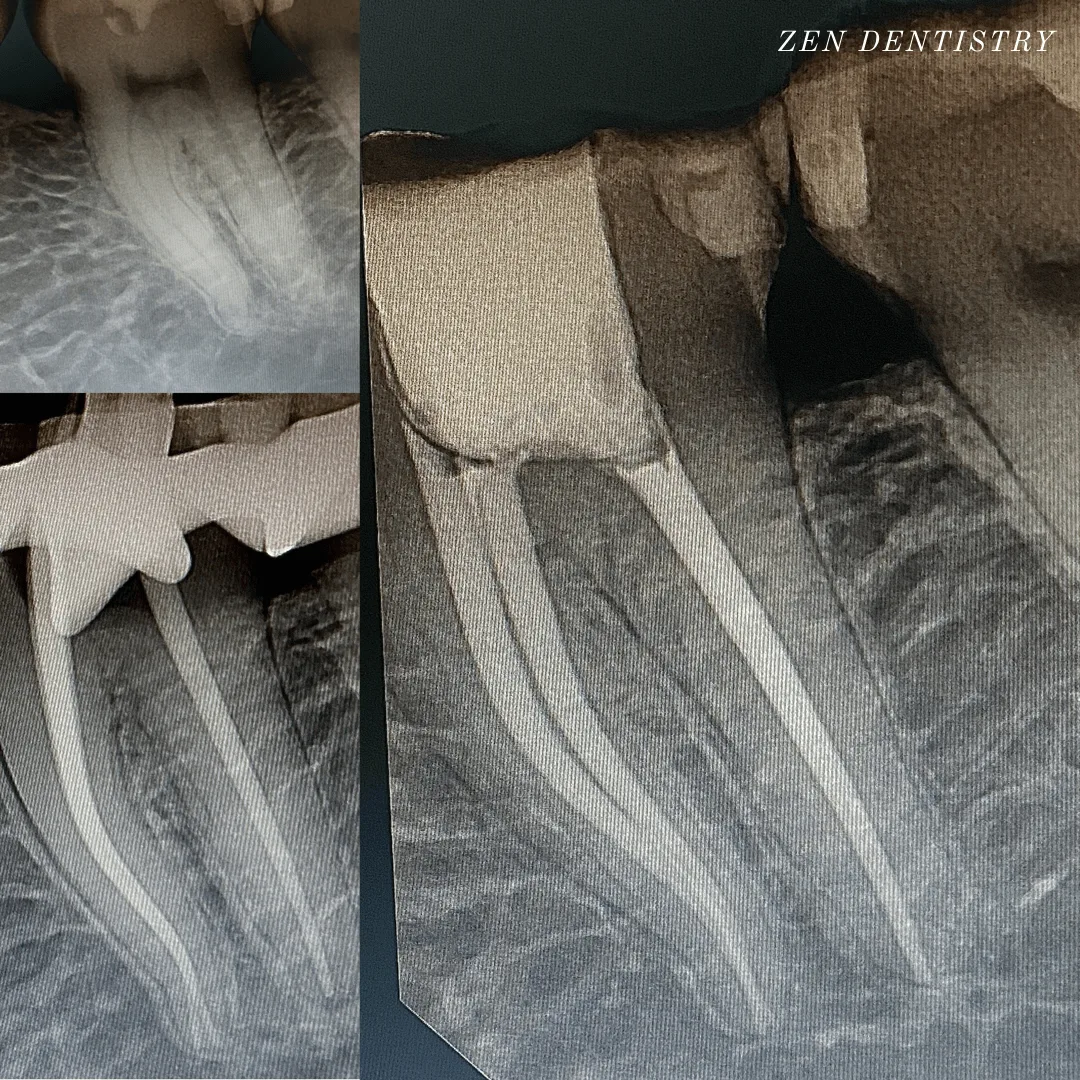

Patient presented with a complaint of severe constant pain that would exaggerate on laying down and biting.

Patient wanted to save the tooth.

A thorough clinical exam, endodontic screening and proper x rays led to the diagnosis of necrotic (dead) pulp due to dental caries with inflamed periodontal ligaments.

A thorough clinical exam, endodontic screening and proper x rays led to the diagnosis of irreversible pulpitis(inflamed pulp tissue) due to secondary dental caries with inflamed periodontal ligaments.

A thorough clinical exam, endodontic screening and proper x rays led to the diagnosis of necrotic pulpal tissue(dead pulp tissue) due to secondary dental caries with inflamed periodontal ligaments.

Patient presented with a complaint of severe constant pain that would exaggerate at night time and wake the patient up from sleep.

A thorough clinical exam, endodontic screening and proper x rays led to the diagnosis of irreversible pulpitis due to gross dental caries involving the pulp.